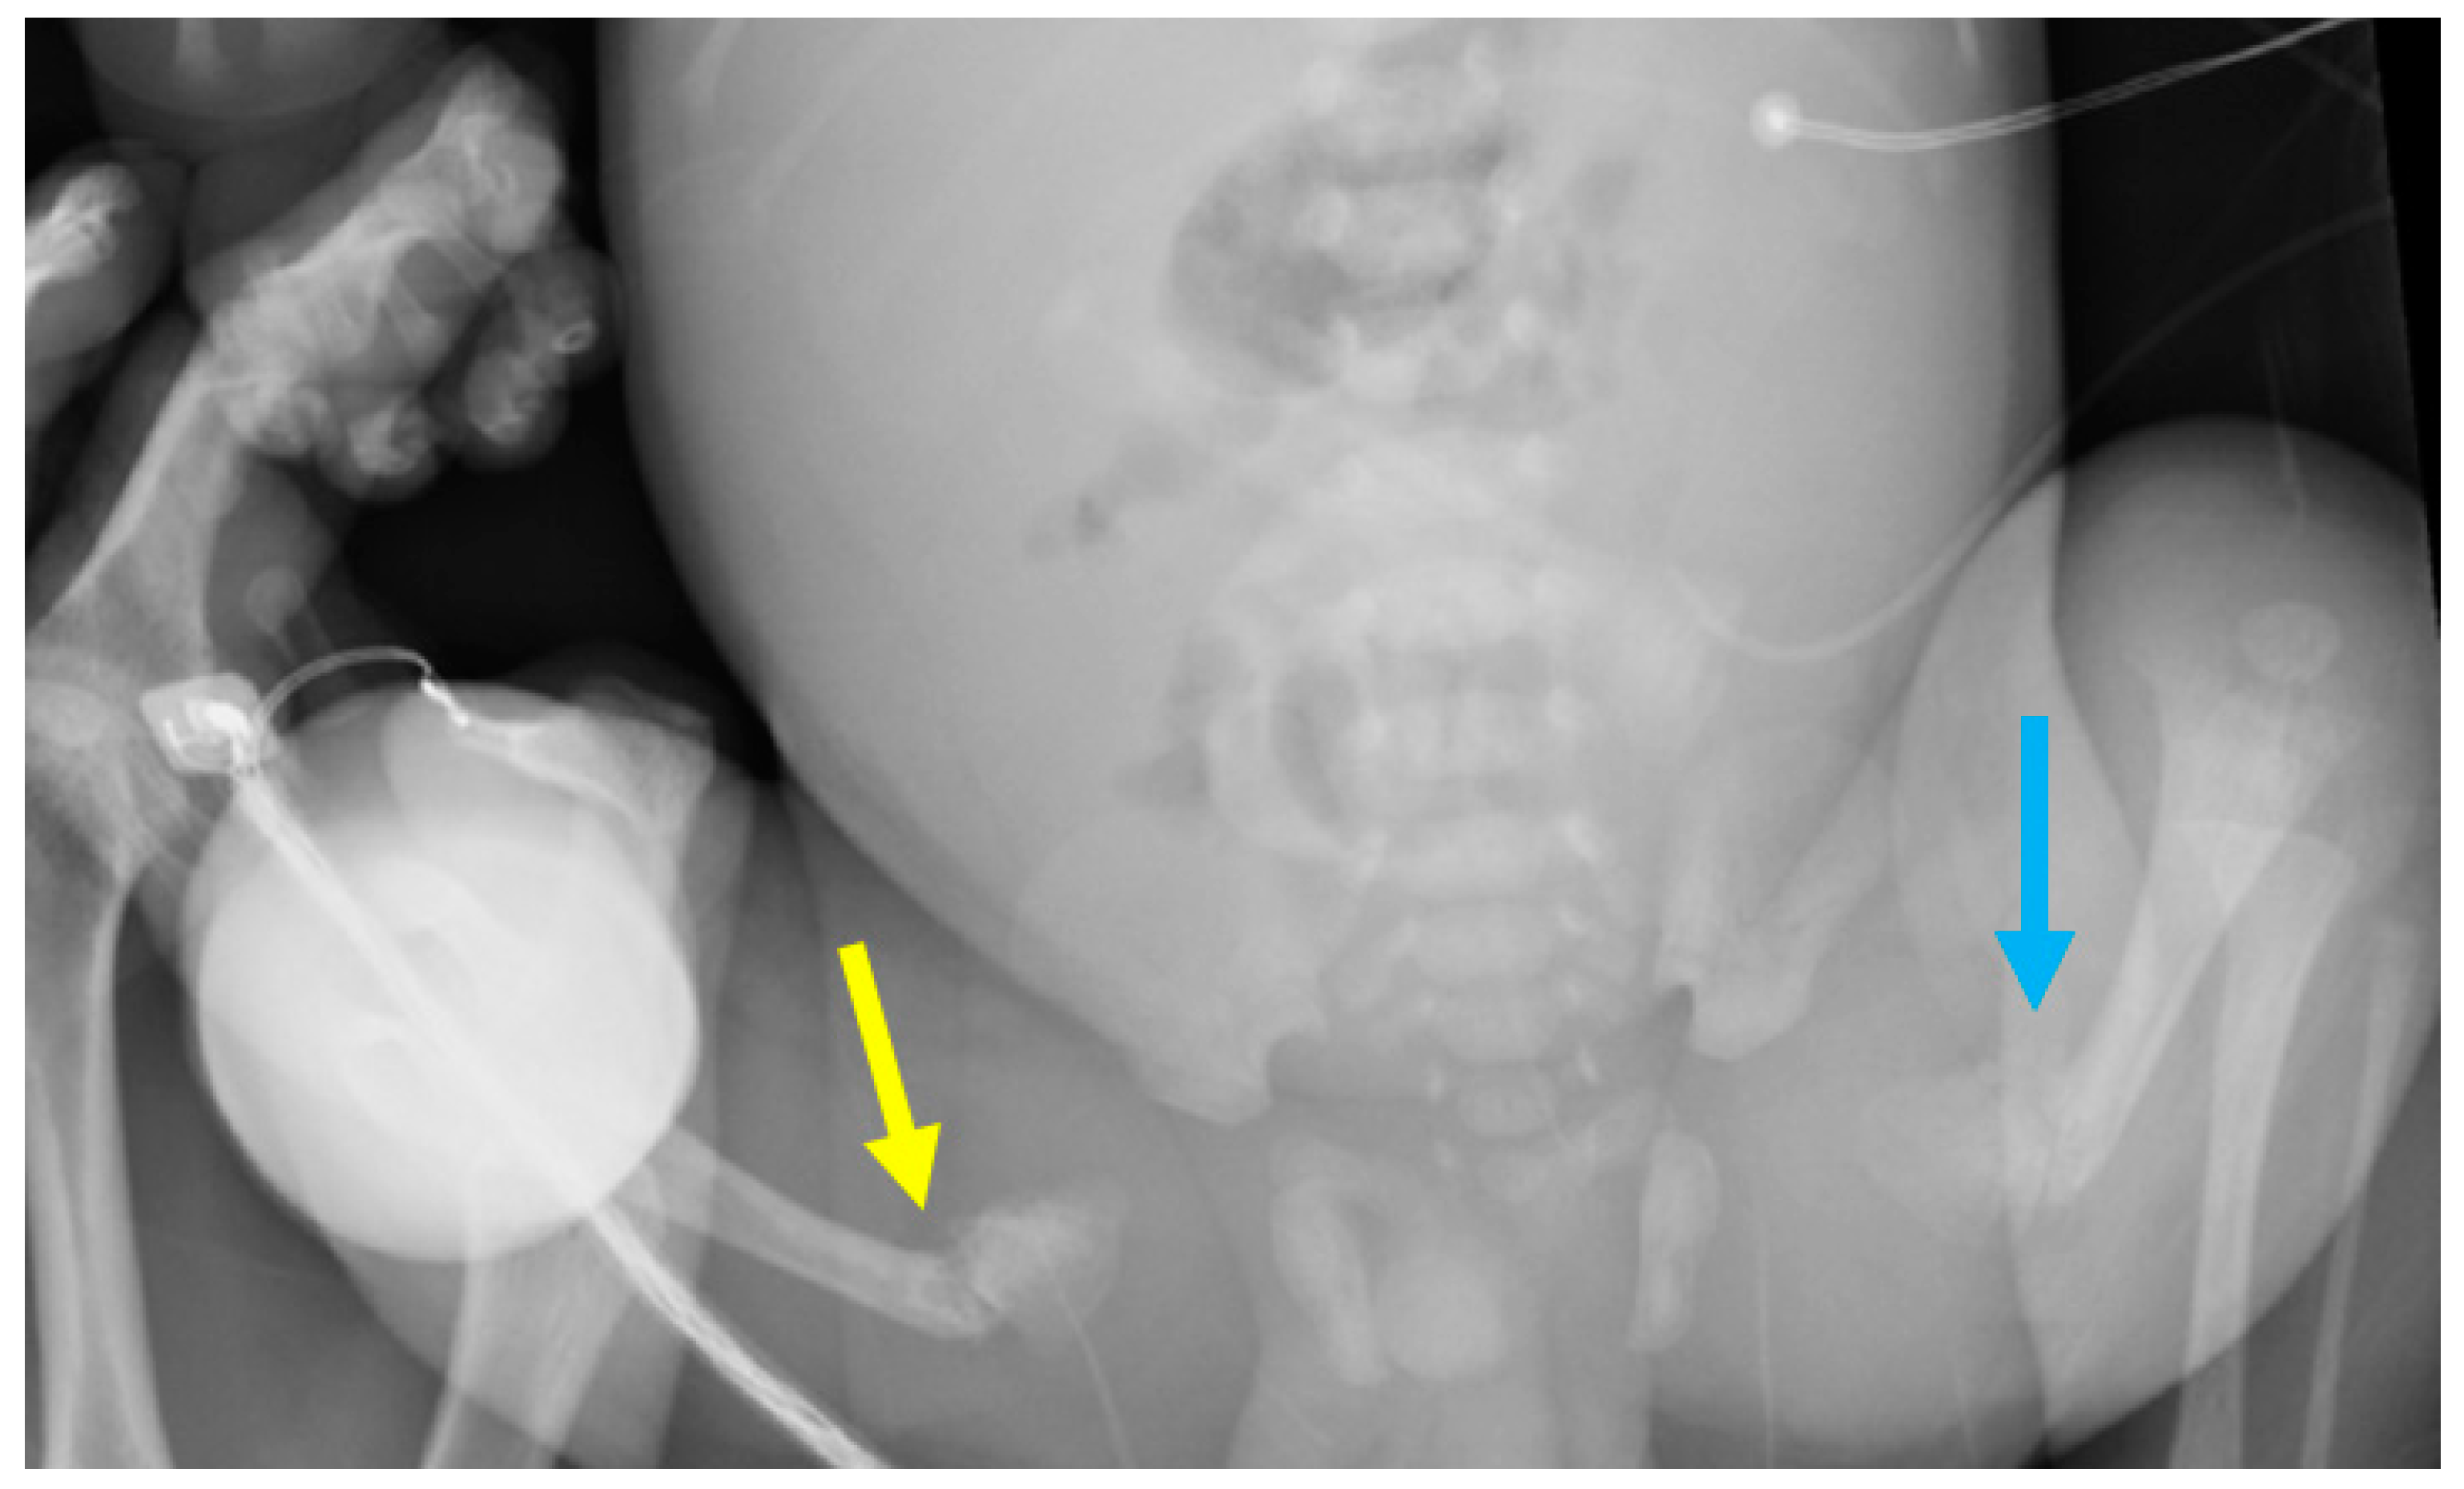

3.1. Phenotypes of the Patient and Parents